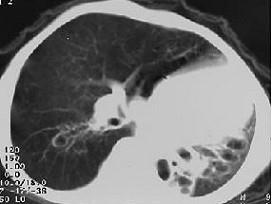

女,8岁,如图所示,最可能诊断为 ( )A、左下肺支气管扩张B、左下肺支气管囊肿C、左下肺隔离症D、左肺发育不全E、左下肺不张

问题 女,8岁,如图所示,最可能诊断为 ( )

选项 A、左下肺支气管扩张 B、左下肺支气管囊肿 C、左下肺隔离症 D、左肺发育不全 E、左下肺不张

答案 D